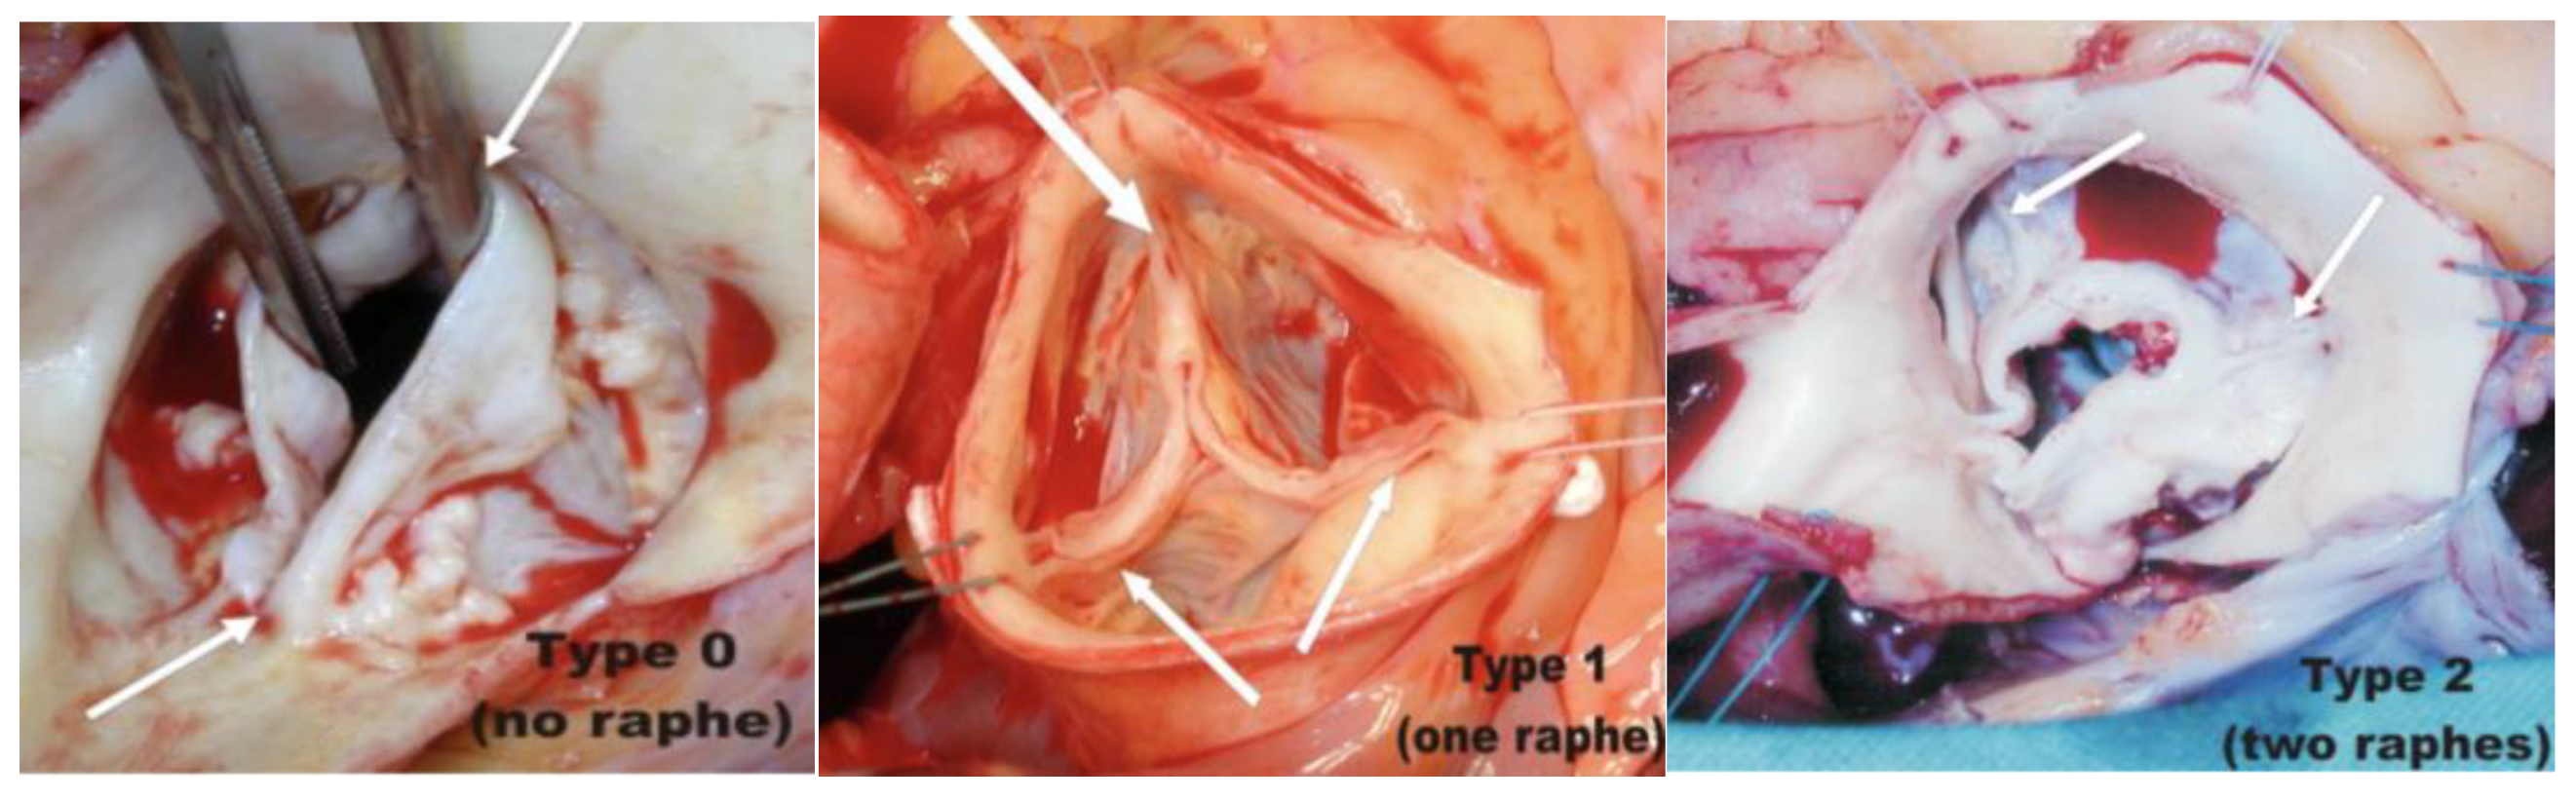

2.2.3. AR Associated with Bicuspid Aortic Valve

- Das, R.; Puri, R. Transcatheter treatment of bicuspid aortic valve disease: Imaging and interventional considerations. Front. Cardiovasc. Med. 2018, 5, 91. [Google Scholar] [CrossRef]

- Sievers, H.-H.; Schmidtke, C. A classification system for the bicuspid aortic valve from 304 surgical specimens. J. Thorac. Cardiovasc. Surg. 2007, 133, 1226–1233. [Google Scholar] [CrossRef]